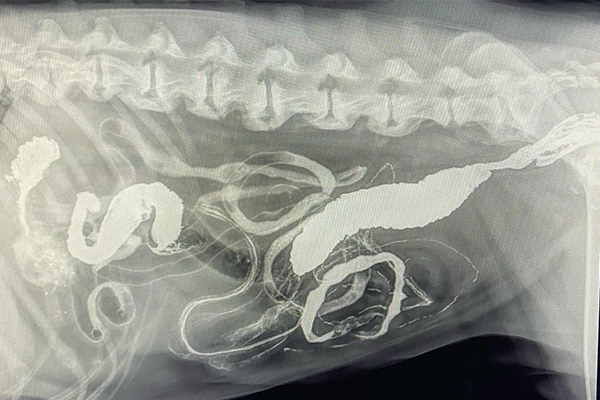

Barium Series

This procedure is a Contrast Study which means that we use a contrast dye that shows up on x-ray and highlights certain structures. Because some objects don’t show up on xray (plastic, fabric, toys, etc), this can help outline it or show us where the obstruction is as it can’t get past.

Our talented Registered Veterinary Technicians administer barium (the contrast liquid) in the mouth and then we take successive X-rays over the next few hours to watch its progress. The first X-ray is almost immediate to catch the outline of the esophagus while the last one may be hours later as it enters the colon .

Flip through the photos to see the progression of barium through the gastrointestinal tract: